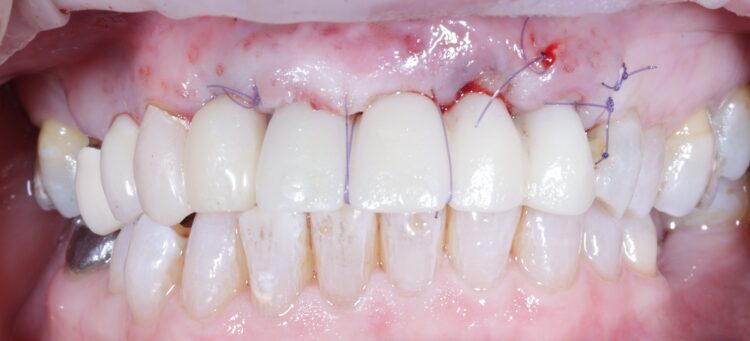

Non-engaging cylinders were placed onto the implants to connect to the pre-fabricated temporary bridge. A premade temporary bridge was connected, contoured and polished, with particular attention paid to the contour of the restoration and suturing with the aim of prosthetically guided soft tissue healing.

Review and reflection

The patient returned to the practice for review two weeks post-surgery and to confirm successful and otherwise uneventful healing. Discomfort was minimal and she reported being very satisfied with the outcome. After a healing period of three months, the patient returned to begin making the final prosthesis. Good soft tissue adaptation was noted around the temporary prosthesis and the buccal contour was successfully maintained.

Upon professional reflection, this case went according to plan, emphasising the importance of meticulous assessment and preparation prior to implant surgery. The guided approach helped to ensure the precise positioning of the implants which facilitated connecting the temporary bridge. This, alongside the implant selection, was crucial for maximising on the limited bone available for primary stability.